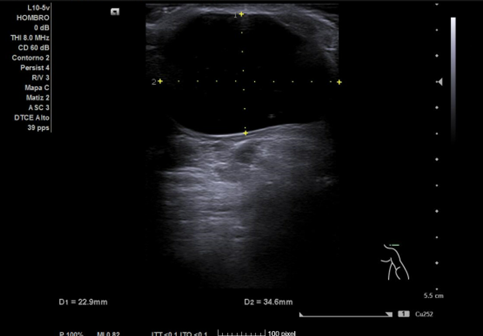

Ecografía hombro izquierdo: se observa una masa de 2,3 x 3,4 cm, anecoica en su totalidad, no tabicada, de bordes bien definidos y sin captación en Doppler.

Diagnóstico final: quiste sinovial probablemente perteneciente a la articulación acromioclavicular.